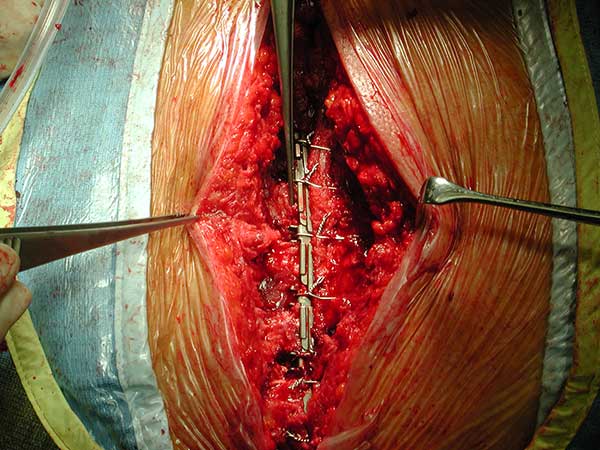

Figure 5. Technique of implantation: the two pliable vertical "fingers" of each unit are bent outwards around the ribs.

To facilitate insertion of the device, the fascia is dissected from the sternal border with electrocautery, and if necessary, perforating vessels are clipped (Figure 2). Once the fascia is mobilized, the hemisternum is elevated by two hand retractors to optimize exposure. The clips are assembled to form a device of a suitable length (up to 5 clips for each one) and the vertical segments of the clips are inserted into the intercostals spaces (Figures 3, 4). The two pliable vertical “fingers” of each unit are then bent outwards to wrap around the ribs, so that the clips are held firmly in place (Figure 5; Video 3). Re-approximation of the sternum is then achieved by means of single interrupted stainless steel wires. Two to 3 are placed through the manubrium, and the others are placed around the grooved arms of the clips at the level of the intercostal spaces (Figures 6, 7). The fascia, subcutaneous layers, and skin are closed in a routine manner. The extra time required for placement of the reinforcement device decreases with experience, and in our hands is approximately 4 to 6 minutes for each hemisternum.